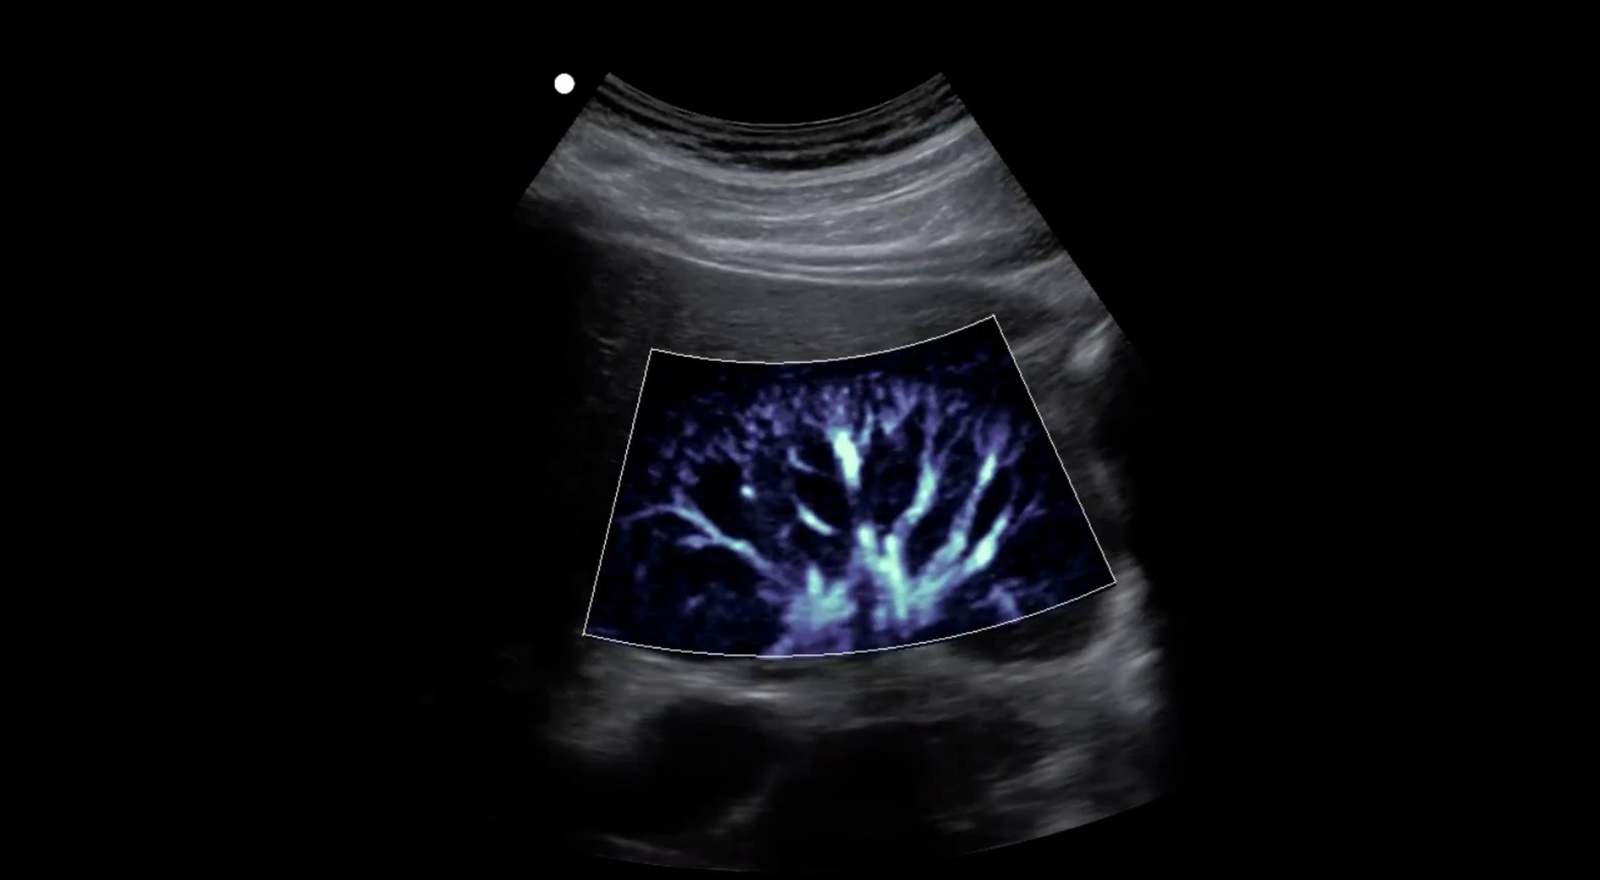

微血流成像 zMicroflow

显著提升肾脏、心肌内膜、淋巴结等组织内部微血管彩色血流信号的显示能力,真实反映血流变化情况